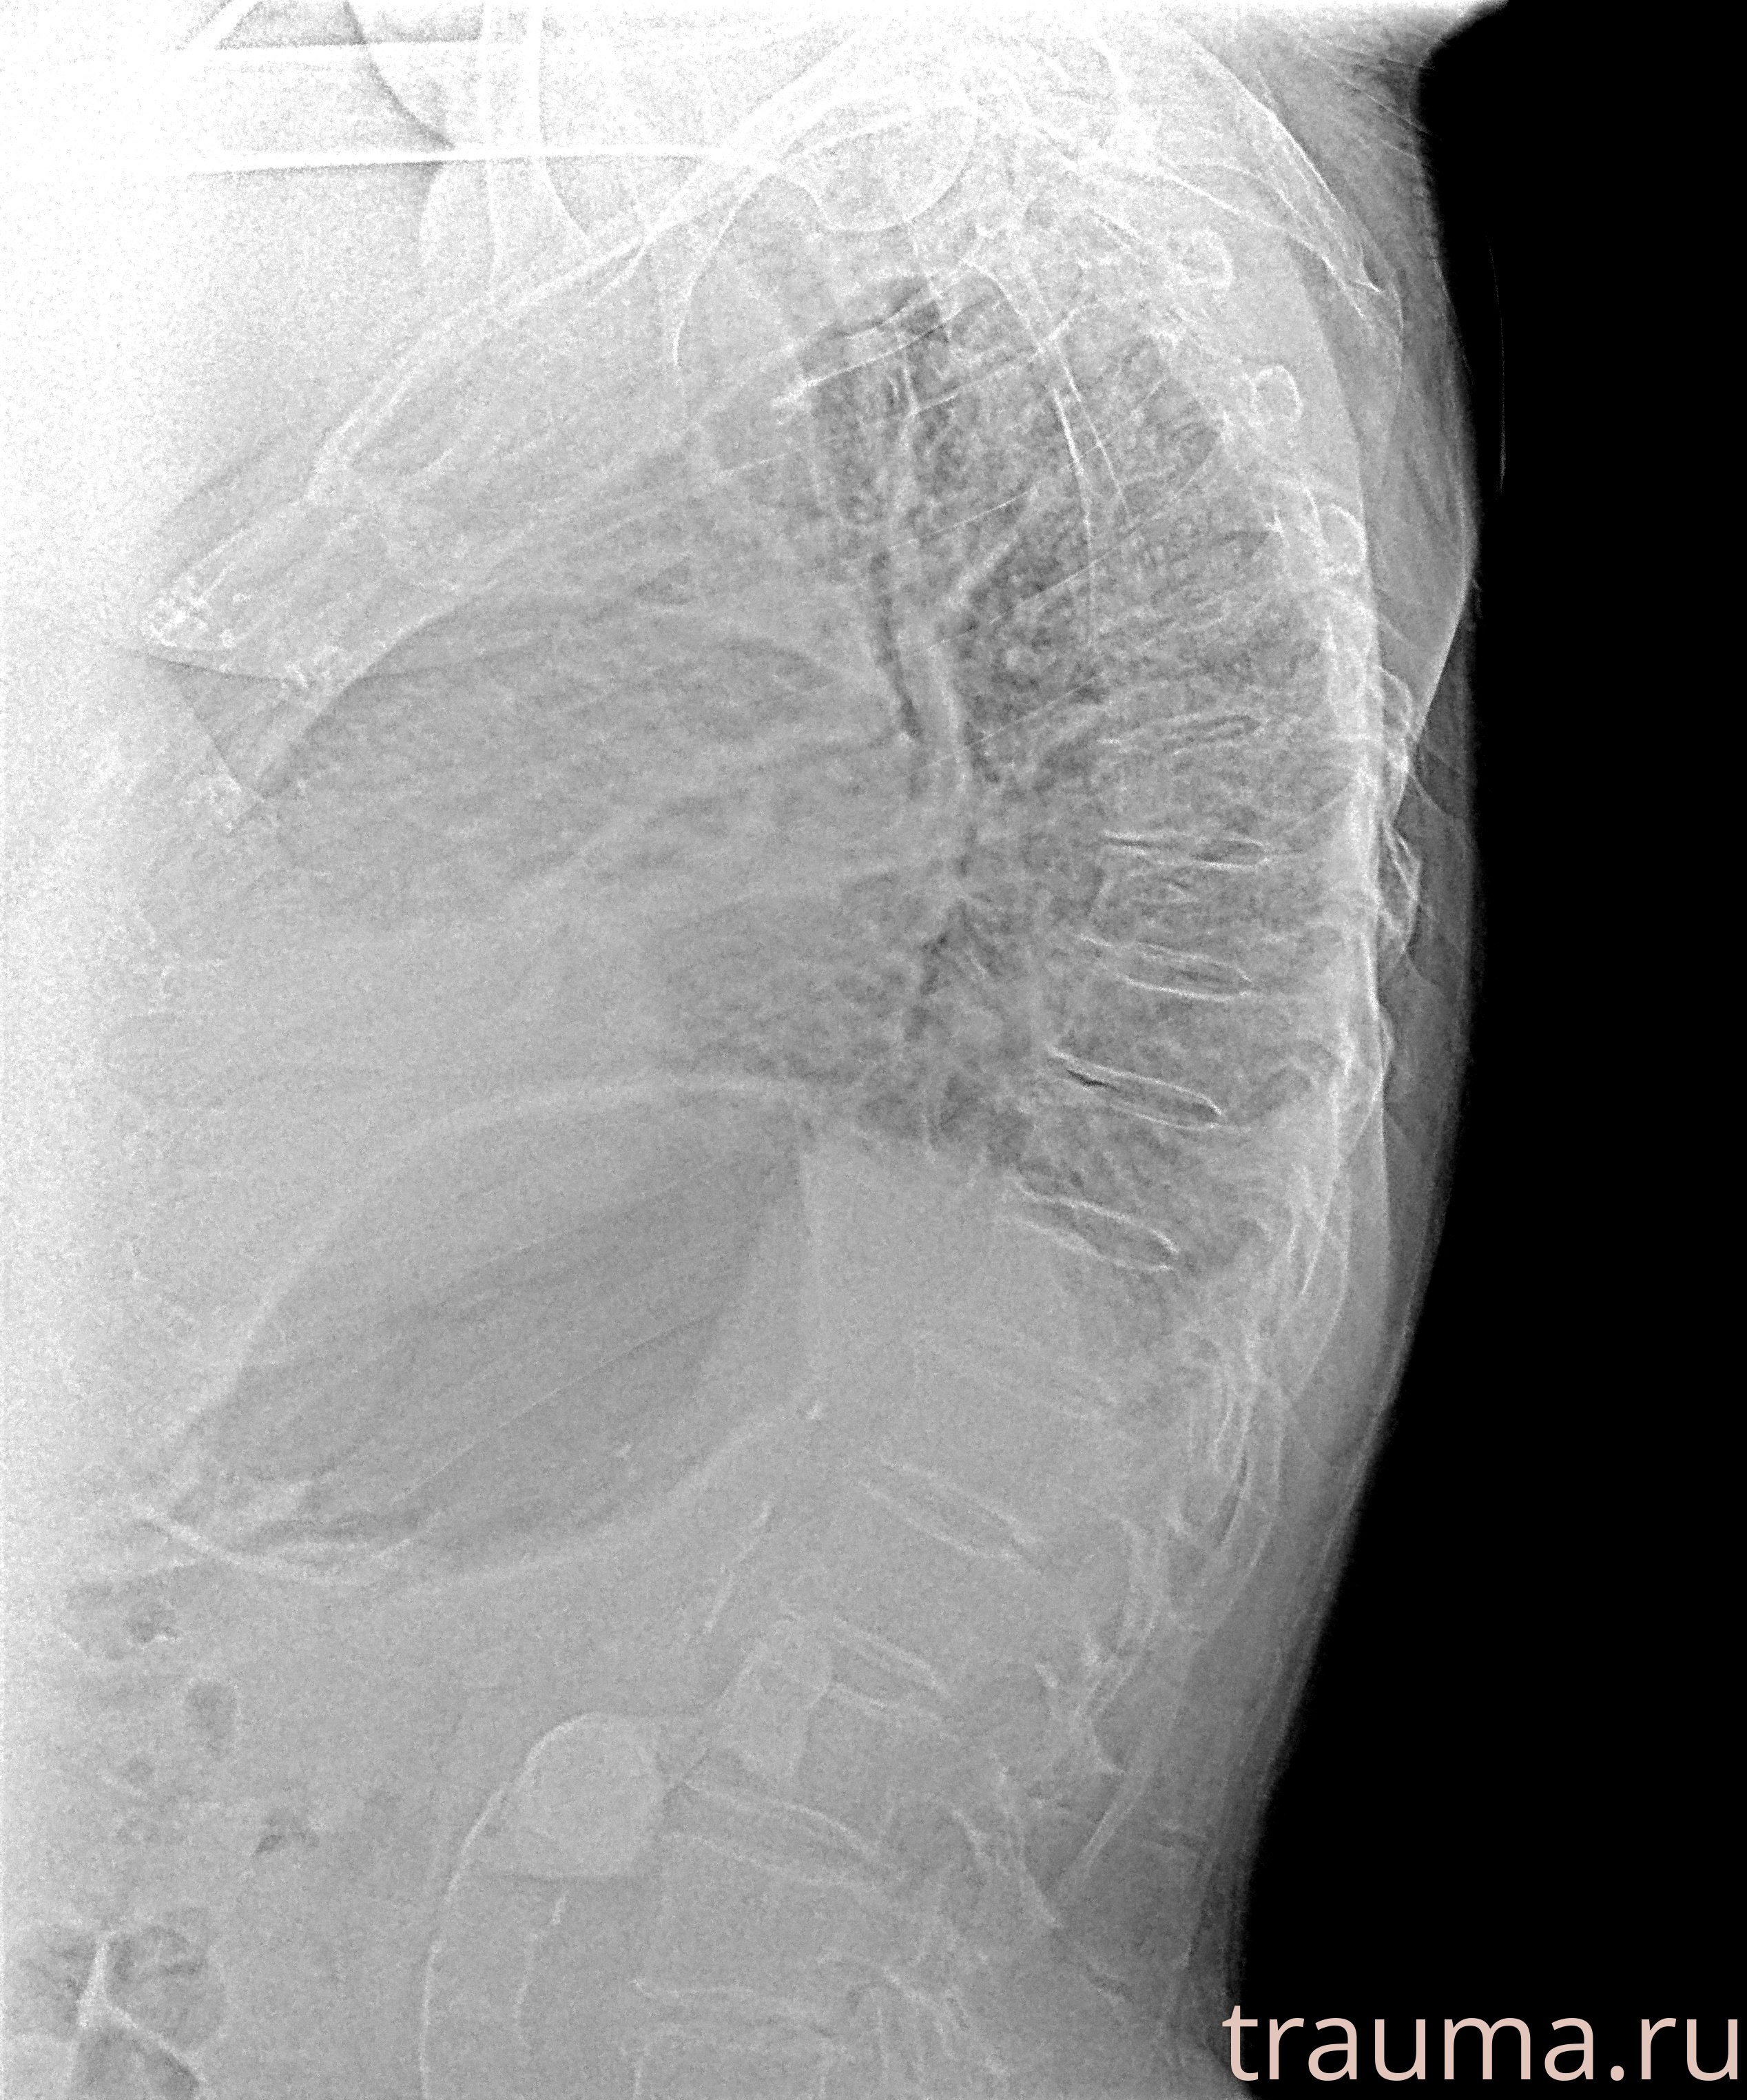

Рентгенограммы

Рентген на дому: по вашему адресу приезжает врач-рентгенолог, травматолог-ортопед с мобильным рентгеновским аппаратом, проводит диагностику травмы или заболевания, делает необходимые рентгенограммы, дает рекомендации по дальнейшему лечению. Получить качественные снимки в домашних условиях возможно благодаря уникальной методике, разработанной МосРентген Центром для института  Склифосовского